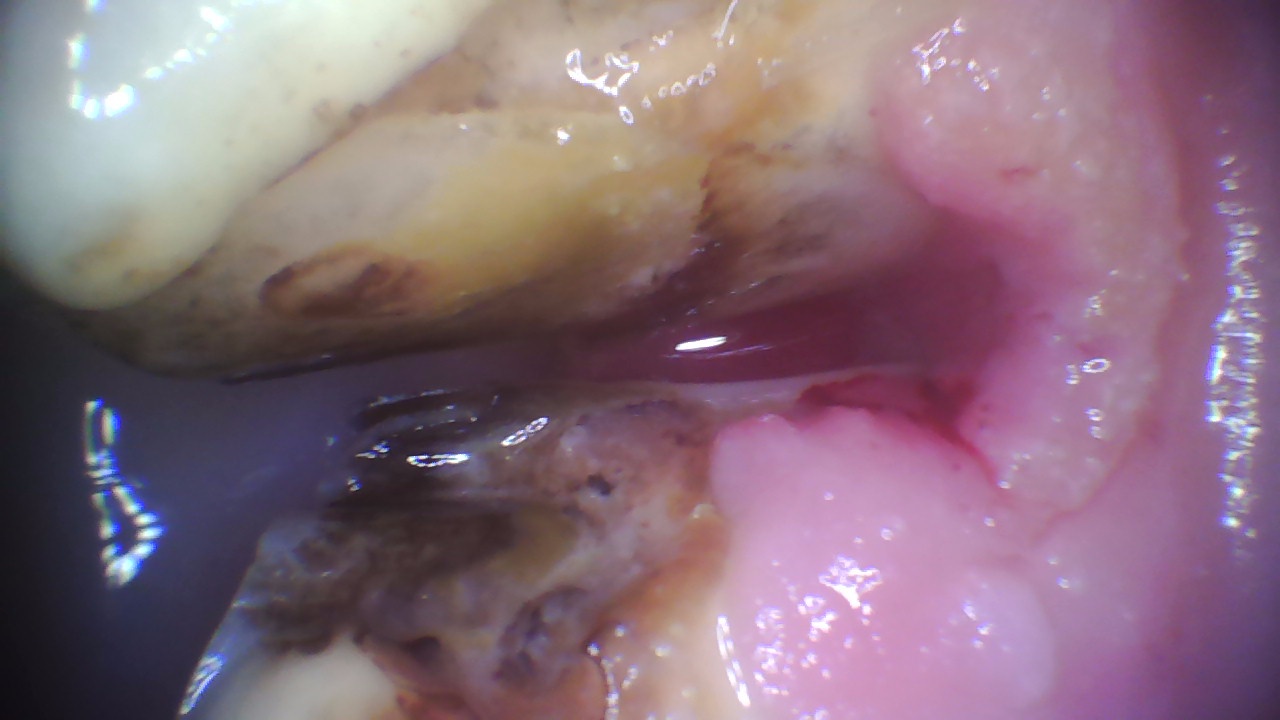

Foderinpackningar är ett tillstånd då det samlas foder mellan hästens tänder. Fodret som packas in mellan tänderna bryts ned av mikroorganismer (bakterier). Nedbrytningsprocessen ger ifrån sig en ”rutten” doft och det är vanligt att drabbade hästar luktar illa ur munnen.

Foderinpackningar kan bli djupa, orsaka kraftig inflammation (även s.k. parodontit som är en inflammation av tandens stödjevävnad) och vara mycket smärtsamma.